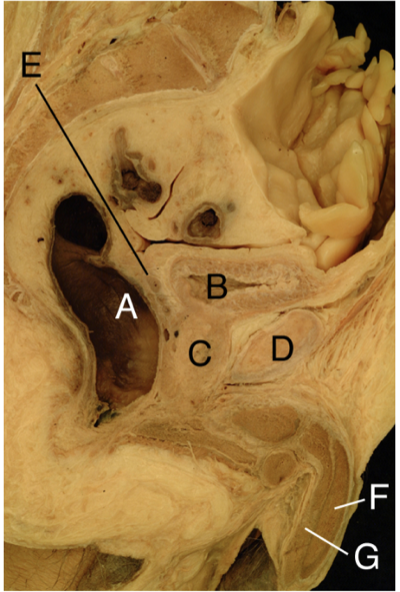

a. ampulla recti

b. vesica urinaria

c. prostata

d. symphysen

e. vesicula seminalis

f. corpus cavernosum

g. corpus spongiosum